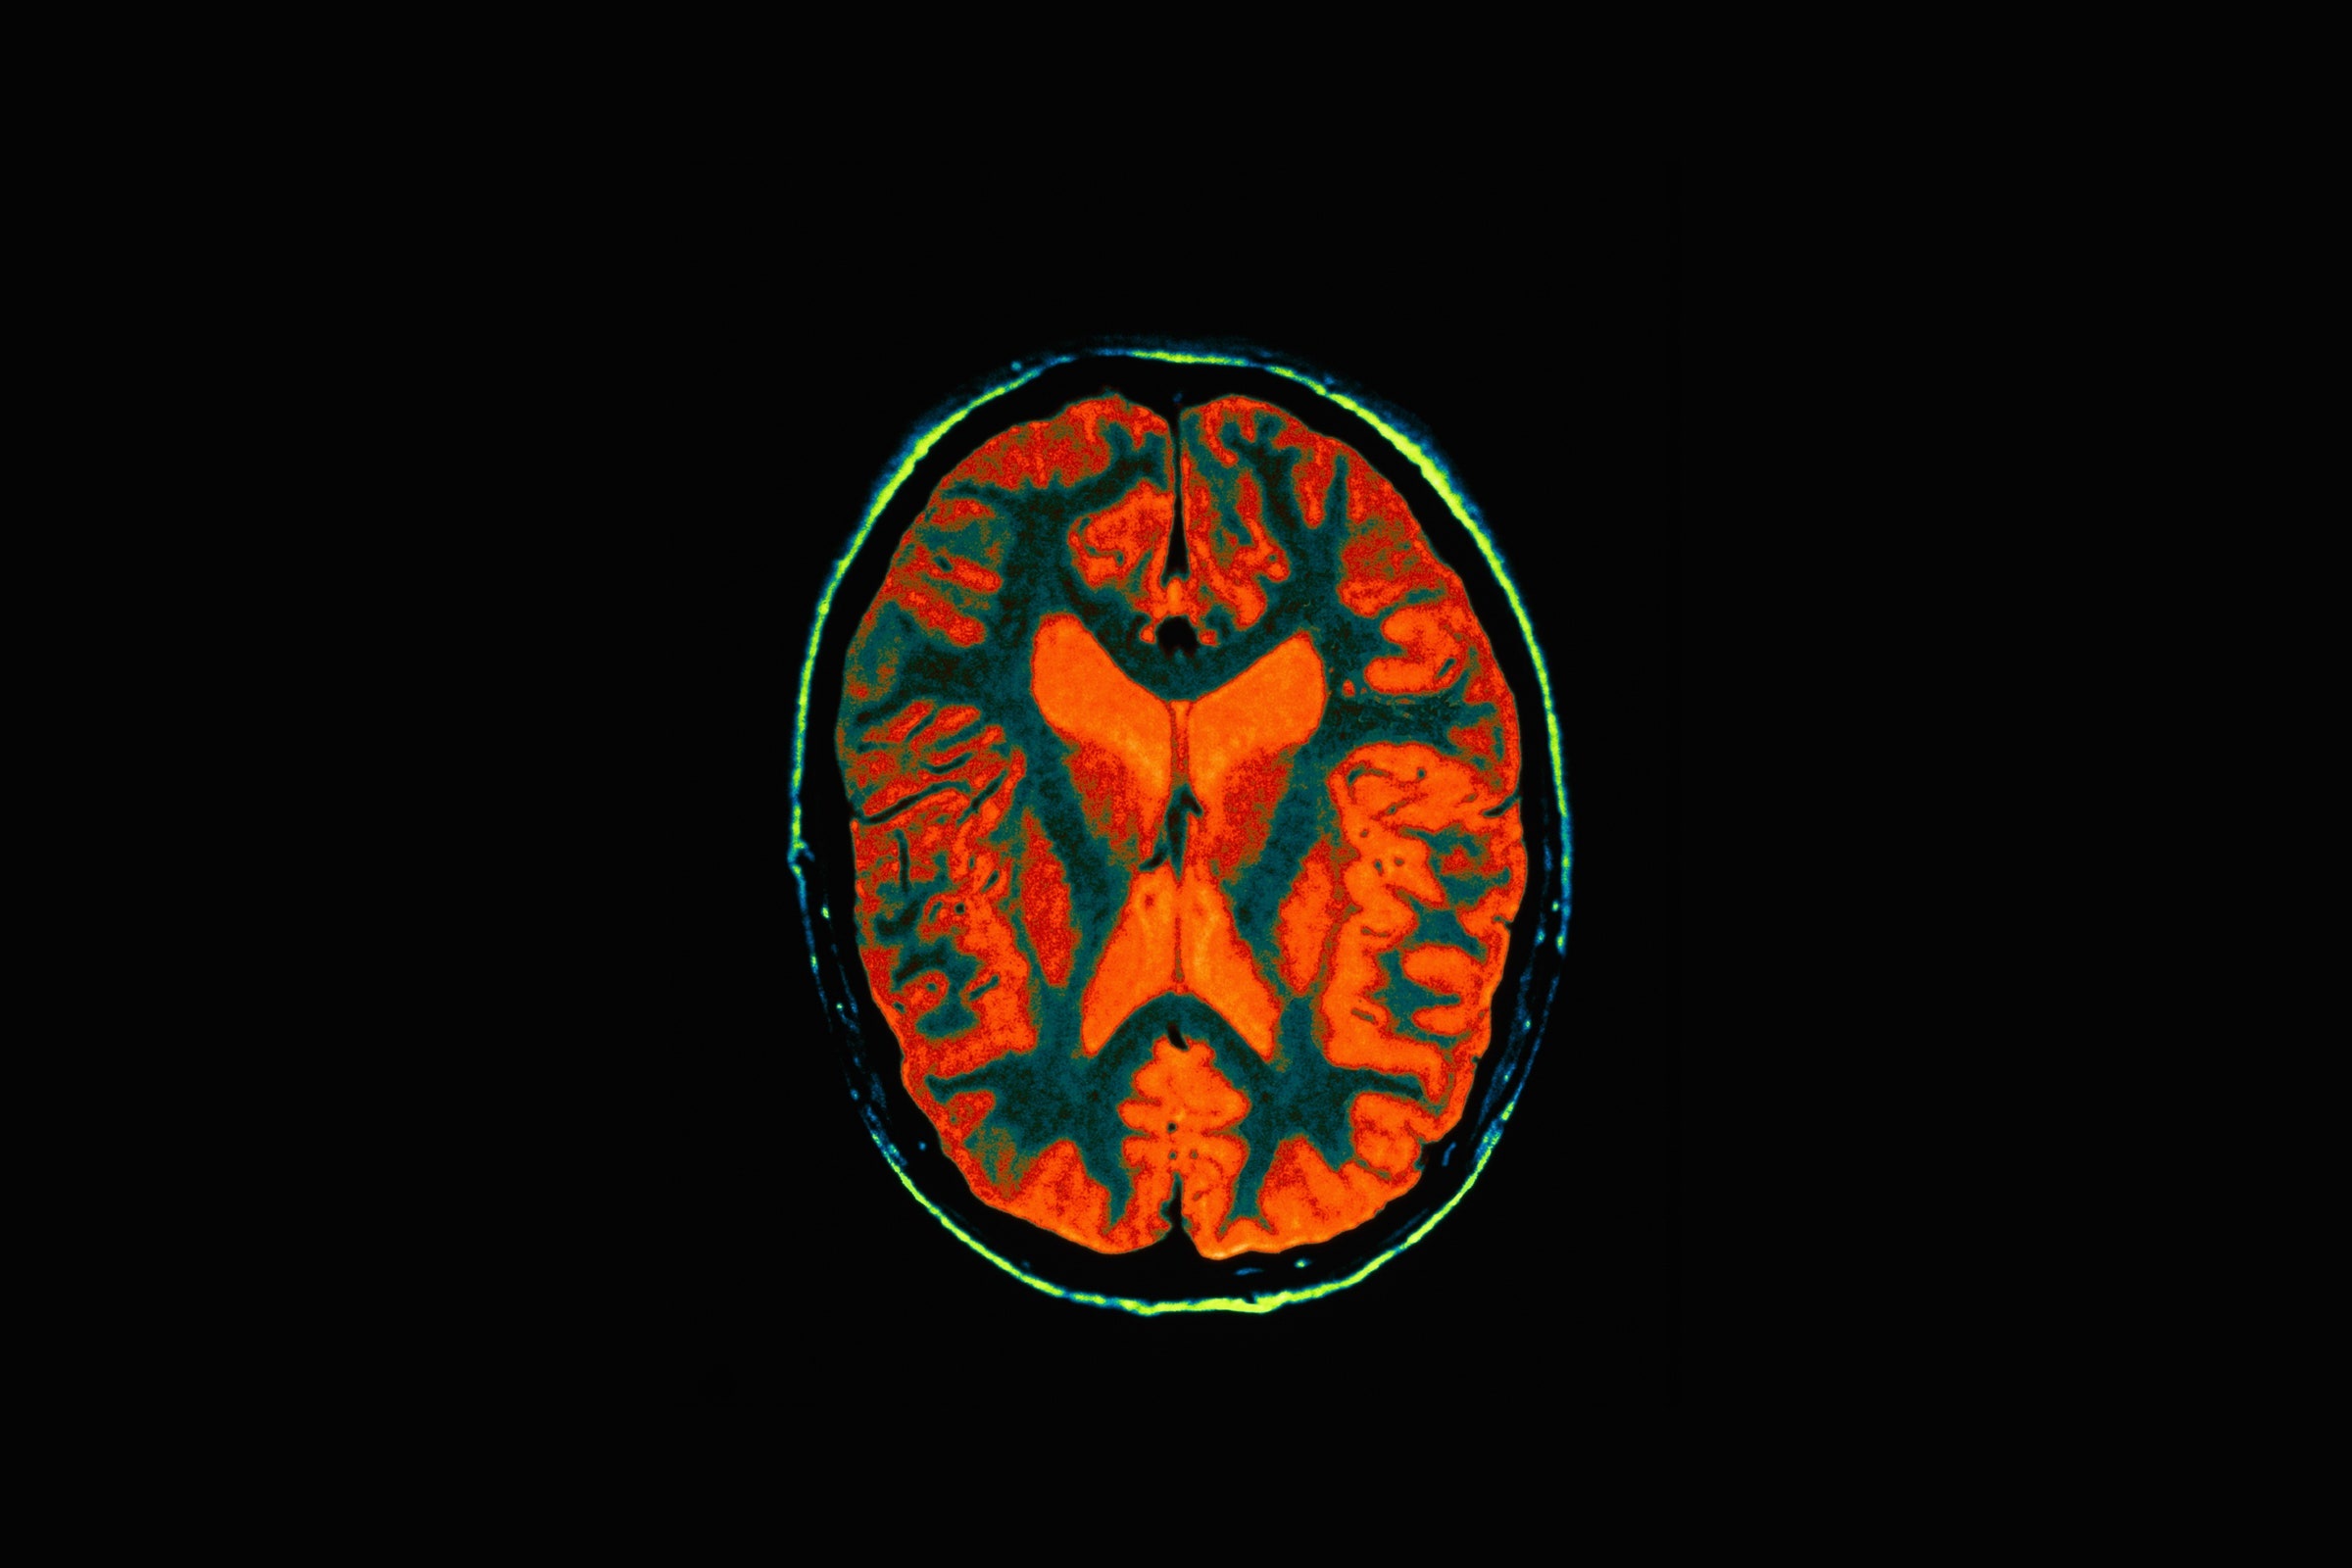

| Một bộ phận của não có nhiệm vụ tạo ra cảm xúc, kích khích những bộ phận khác trong não ghi lại ký ức. |

"Khi quan sát bộ não, các nhà khoa học cho thấy hạch hạnh nhân – một bộ phận của não có nhiệm vụ tạo ra cảm xúc – kích khích những bộ phận khác trong não ghi lại ký ức". Đó là lý do vì sao chúng ta thường nhớ những sự kiện có cảm xúc mạnh lâu hơn.

"Nghiên cứu ảnh chụp thần kinh cho thấy não người tăng cường hoạt động ở vùng chẩm – đỉnh khi ghi nhớ bằng phương pháp cung điện ký ức", Shaw cho biết. "Có nghĩa là kỹ thuật này sử dụng nhiều bộ phận thường dành cho các giác quan khác trong não hơn, như thùy đỉnh cho khả năng định hướng và thủy chẩm cho khả năng thị giác".